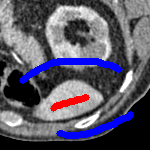

3 Alternative Selective Segmentation Models

We now introduce two recent methods that incorporate user input to perform selective segmentation. Each involves input in the form of foreground/background regions to indicate relevant structures of interest. An example of this can be seen in Fig. 18, where red regions indicate foreground and blue regions indicate background. We compare against the work of Nguyen et al. Nguyen:12 , which uses a similar convex relaxation framework to the proposed approach, and Dong et al. SRW , which uses a variation of the random walk approach. We summarise the essential aspects of each approach in the following.

7.4 Alternative Selective Methods

In order to further establish the robustness of our method, we now introduce the results of testing our approach against competing interactive segmentation methods on a larger data set. The results are presented in Fig. 17, showing a boxplot of accuracy in terms of TC on a set of 30 CT images (excluding outliers). The target structure we consider is the spleen, as this consists of a relatively homogeneous foreground, appropriate for the approach considered. The data has been manually contoured providing ground truth data for the image set. We compare CAC Nguyen:12 and SRW SRW against our method with five variations of user input for each image. It is worth emphasising here that the input used in the tests is identical for each approach and was not refined in any way. It was designed to mimic what a user, unfamiliar with each approach, might select intuitively. A representative example for three images is shown in Fig. 18. This shows foreground (red) and background (blue) user input regions. For our method, we define the red region as as discussed in §1 and enforce hard constraints on the blue region. We refer to the results of the proposed approach using this input as Ours (i). We also include results of randomising the user input in an identical way to §7.3. For each image we generate 1000 simulated user input choices, which we present as Ours (ii). It is important to note that the difference between Ours (i) and (ii) is only the definition of . The method and parameters are fixed between each.

The performance of CAC Nguyen:12 is very good, as shown in Fig. 17. We have included an additional figure to highlight the difference between CAC and Ours (i) and (ii) more precisely. This is shown in Fig. 19 (this is the same as Fig. 17 with TC restricted to [0.8,1]). Here we can see that the proposed approach has a slightly better median (0.96 compared to 0.94) and is generally more consistent than CAC. This is particularly evident when considering the worst TC results of CAC () against ours ().

In Fig. 17 it can be seen that our method exceeds the performance of SRW by a large margin (0.66 compared to 0.95). One possible reason for this is that the input used, as displayed in Fig. 18, is restricted to be as intuitive as possible. SRW is capable of achieving improved results with more elaborate foreground/background input. However, it is generally reliant on a trial and error approach which is not ideal in practice. This highlights an important advantage of our method. It is able to achieve a high standard of results with simple user input. This is reinforced by considering Ours (ii), where the results of 30000 random variations of the user input does not cause a drop off in accuracy compared to the 150 manual user input selections. Again, this can be seen more clearly in Fig. 19. In fact, the results for the proposed approach with the random input are slightly better than with the manual input. This underlines the robustness to user input in the model, which is a vital aspect of selective segmentation.